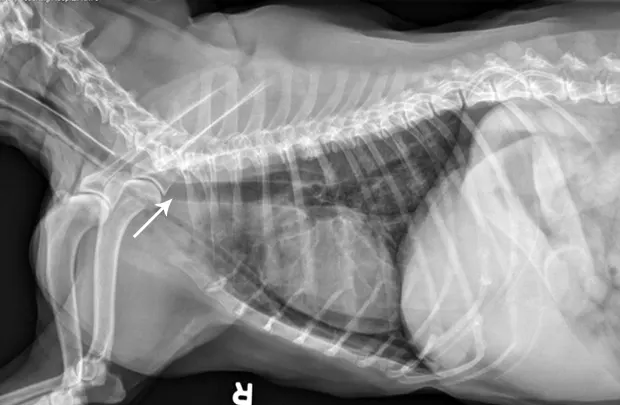

Ensure the tube is properly positioned via lateral radiography (A).

If placement is uncertain, infuse a small amount of nonionic contrast material to differentiate the esophagostomy tube from the endotracheal tube or jugular catheter (B).

If the tube is in the trachea, the portion running in the proximal cervical region will be visibly ventral to the esophagus on radiography (C).

FIGURE A